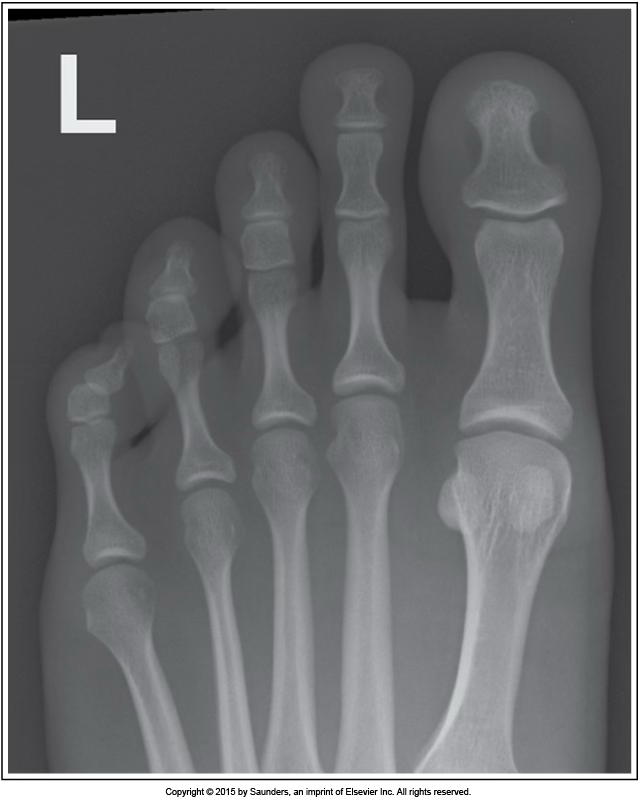

AP toe

accurate positioning